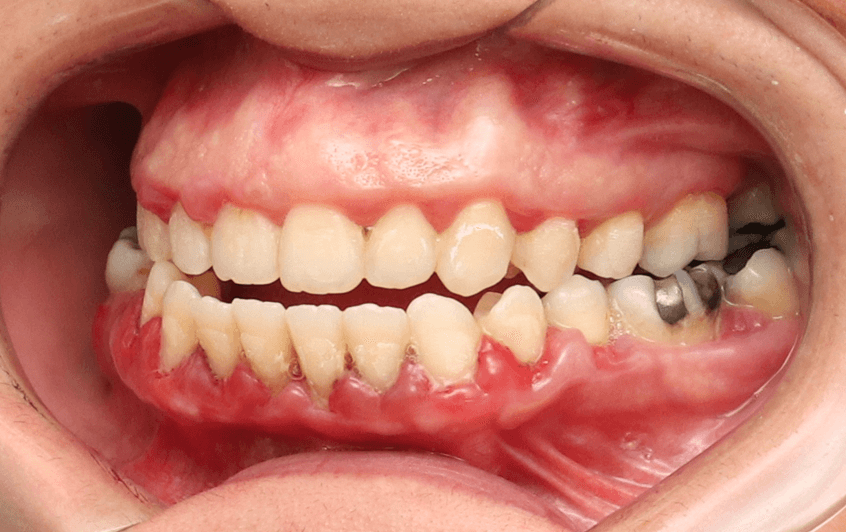

Doença Periodontal Ativa:

Pacientes com doenças gengivais avançadas podem não ser candidatos ideais para alinhadores, pois a movimentação dentária pode agravar a condição.

O tratamento ortodôntico em pacientes com doença periodontal deve ser realizado com muito critério e cuidado, sendo contraindicado o tratamento ortodôntico em pacientes com doença periodontal ativa.

Perda Óssea Significativa:

A perda óssea ao redor dos dentes pode comprometer a capacidade do alinhador de mover os dentes de forma eficaz e segura.

A movimentação ortodôntica pode exacerbar essa mobilidade, o que aumenta o risco de complicações como a perda do dente ou uma piora da condição da gengiva.